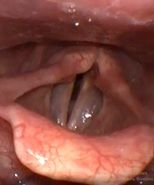

Рис 2А. Двусторонний паралич гортани. До операции.

Рис 2Б Двусторонний паралич гортани. 7 сутки после операции